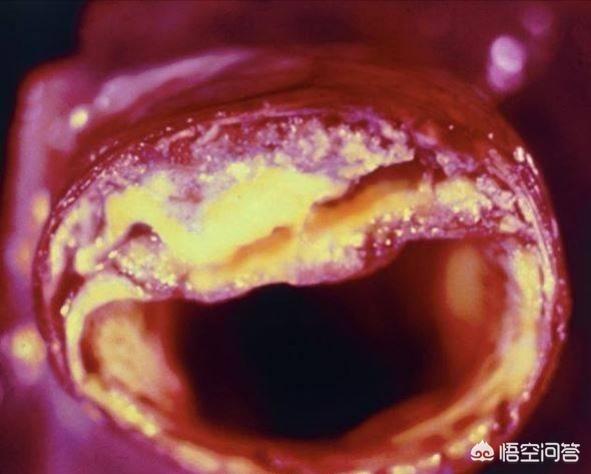

Sous l'influence de facteurs de risque cardiovasculaire tels que l'hyperlipidémie, la paroi interne des vaisseaux sanguins est progressivement endommagée et les lipides en excès dans le sang se déposent progressivement sous la paroi du vaisseau, formant un noyau lipidique athéromateux jaune, et finalement une chape fibreuse se forme dans le noyau lipidique, ce qui constitue le processus de formation de la plaque artérielle. La plaque est un facteur de risque conduisant à l'athérosclérose, et les plaques qui ont des problèmes de stabilité et se rompent peuvent conduire à une agrégation plaquettaire réactive. L'agrégation réactive des plaquettes peut même conduire à la formation de caillots sanguins, bloquant les vaisseaux artériels et provoquant des maladies cardiovasculaires infarciques. Ce qu'il faut faire, c'est prévenir la formation de la plaque par des médicaments et des exercices raisonnables, essayer de maintenir la stabilité de la plaque existante, ralentir le processus d'athérosclérose et empêcher la rupture de la plaque d'entraîner un risque plus élevé.

La plaque a la plaque veineuse, la plaque artérielle, c'est dans le rôle de multiples facteurs étiologiques, en raison de la lipidation de la précipitation, pour dire les choses franchement, c'est-à-dire, vous graissez plus, la digestion et l'utilisation ne peut pas être, dans les lipides sanguins quatre et d'autres facteurs multiples sous l'influence de et puis des dommages à l'intima, le dépôt à la couche interne des vaisseaux sanguins, la formation d'un noyau lipidique jaune athéromateux, et finalement dans la formation d'un noyau fibreux sur le noyau lipidique, qui est normalement très stable, si la coiffe fibreuse est soumise à une inflammation soutenue. la chape fibreuse se rompt, la plaque s'écoule et les plaquettes sanguines dans le mariage éclair donnent naissance à un enfant perturbateur, appelé thrombus, qui se promène pour semer le trouble, se spécialise dans les mauvaises actions pour bloquer les vaisseaux sanguins, le thrombus dans la lumière des vaisseaux sanguins devient plus étroit en même temps, mais aussi se rompt, déclenchant des événements vasculaires cardio-cérébraux et cérébraux aigus, tels que l'accident vasculaire cérébral, l'infarctus du myocarde, l'embolie pulmonaire, l'insuffisance rénale, les veines variqueuses, etc. etc. Par conséquent, l'élimination de la plaque ne permet pas seulement de déboucher les vaisseaux sanguins, mais aussi de prévenir les accidents cardiovasculaires et cérébrovasculaires aigus, ce qui est dans l'esprit de tout le monde.

La plaque artérielle est une série de réactions inflammatoires déclenchées par des lésions de la paroi artérielle sous l'effet de multiples facteurs étiologiques, avec la formation ultérieure d'une plaque athéromateuse secondaire. La formation de la plaque est plus nocive pour le corps humain, elle rétrécit la lumière du vaisseau sanguin en même temps, elle peut aussi se rompre, déclenchant des événements cardiovasculaires aigus, par conséquent, l'élimination de la plaque non seulement débouche le vaisseau sanguin, mais prévient également les événements cardiovasculaires aigus, qui sont le battement de cœur de tous les patients. Pour le traitement de la plaque, nous pouvons commencer par la cause de la maladie, comme le contrôle des lipides sanguins, de la tension artérielle, de la glycémie, etc., ainsi que le changement d'un mauvais mode de vie, comme un régime pauvre en sel et en cholestérol, l'augmentation de l'exercice, l'arrêt du tabac et la limitation de l'alcool, etc. ou, en plus du traitement ci-dessus, nous pouvons donner des médicaments, et le choix du médicament est la statine, comme l'atorvastatine, la reserpulvastatine et ainsi de suite sont couramment utilisés dans le traitement des plaques d'athérome, et le choix exact du traitement doit être formulé sous la direction d'un médecin spécialiste. Le choix exact du traitement doit être formulé sous la direction d'un médecin spécialiste. Le plan de traitement spécifique doit être formulé sous la direction de médecins spécialistes.

Le processus de formation de la plaque passe par plusieurs étapes : tout d'abord, l'endothélium du vaisseau sanguin est endommagé, comme si la couche protectrice de la surface interne du vaisseau sanguin était "brisée" ; les macromolécules de graisses présentes dans le sang sont transportées par une sorte de substance appelée lipoprotéine de basse densité dans la couche intima-média de la paroi du vaisseau sanguin, où elles s'accumulent en grandes quantités ; la paroi du vaisseau sanguin s'épaissit et le traitement médical consiste à épaissir la couche intima-média de plus d'un millimètre, ce qui est considéré comme de l'athérosclérose. Lorsque l'épaississement de la couche intima-média dépasse 1 mm, on parle d'athérosclérose, telle que l'agrégation locale en une masse, c'est-à-dire la plaque précoce.

Au début de la formation de la plaque, l'accumulation de graisse provoque une série de réactions inflammatoires ; en fait, la graisse est constamment oxydée, dénaturée et forme des substances ressemblant à de la bouillie ; ces substances détruisent la structure normale des vaisseaux sanguins et deviennent partie intégrante des vaisseaux sanguins ; à ce moment-là, la matière lipidique est principalement à l'état liquide, ce que l'on appelle généralement des taches molles.